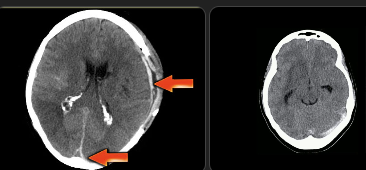

Sinal do Delta Vazio (trombose venosa cerebral).

ANTICOAGULEEEE, ainda que se sangrar com intraparenquimatosa